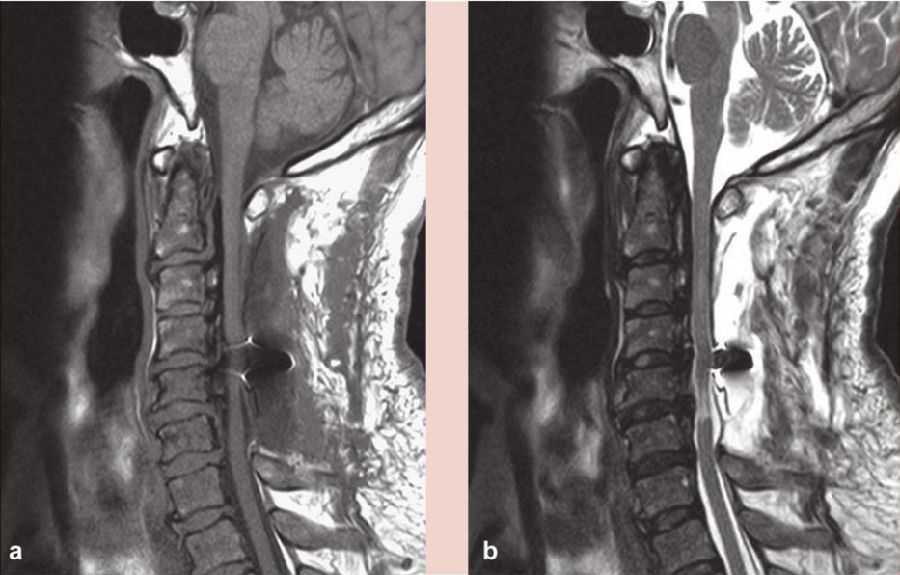

术后给予激素、补液及支持对症治疗,右手麻木较前好转,右侧肢体出现无力,左侧肢体出现麻木,疼痛感不明显,经康复治疗后,右手环指及小指仍感无力,余肢体麻木及无力较前好转,仍对生活及工作有影响。复查颈椎磁共振(MRI)示:C2-6椎板减压及内固定术后状态(图2),C4-6脊髓稍变细,以 C5-6节段显著,C2-6后纵韧带钙化(图2);CT三维重建钉棒系统位置良好(图3);术后3个月复查磁共振(MRI),髓内异常信号较前缩小,颈椎生理曲度变直(图4);术后11个月复查磁共振(MRI)示C4-5、C4-6椎间盘突出,脊髓受压明显,颈椎生理曲度进一步变直(图5)。

图2 术后1周磁共振(MRI)示C4-6脊髓稍变细,髓内可见变性信号

a. T1像;b. T2像